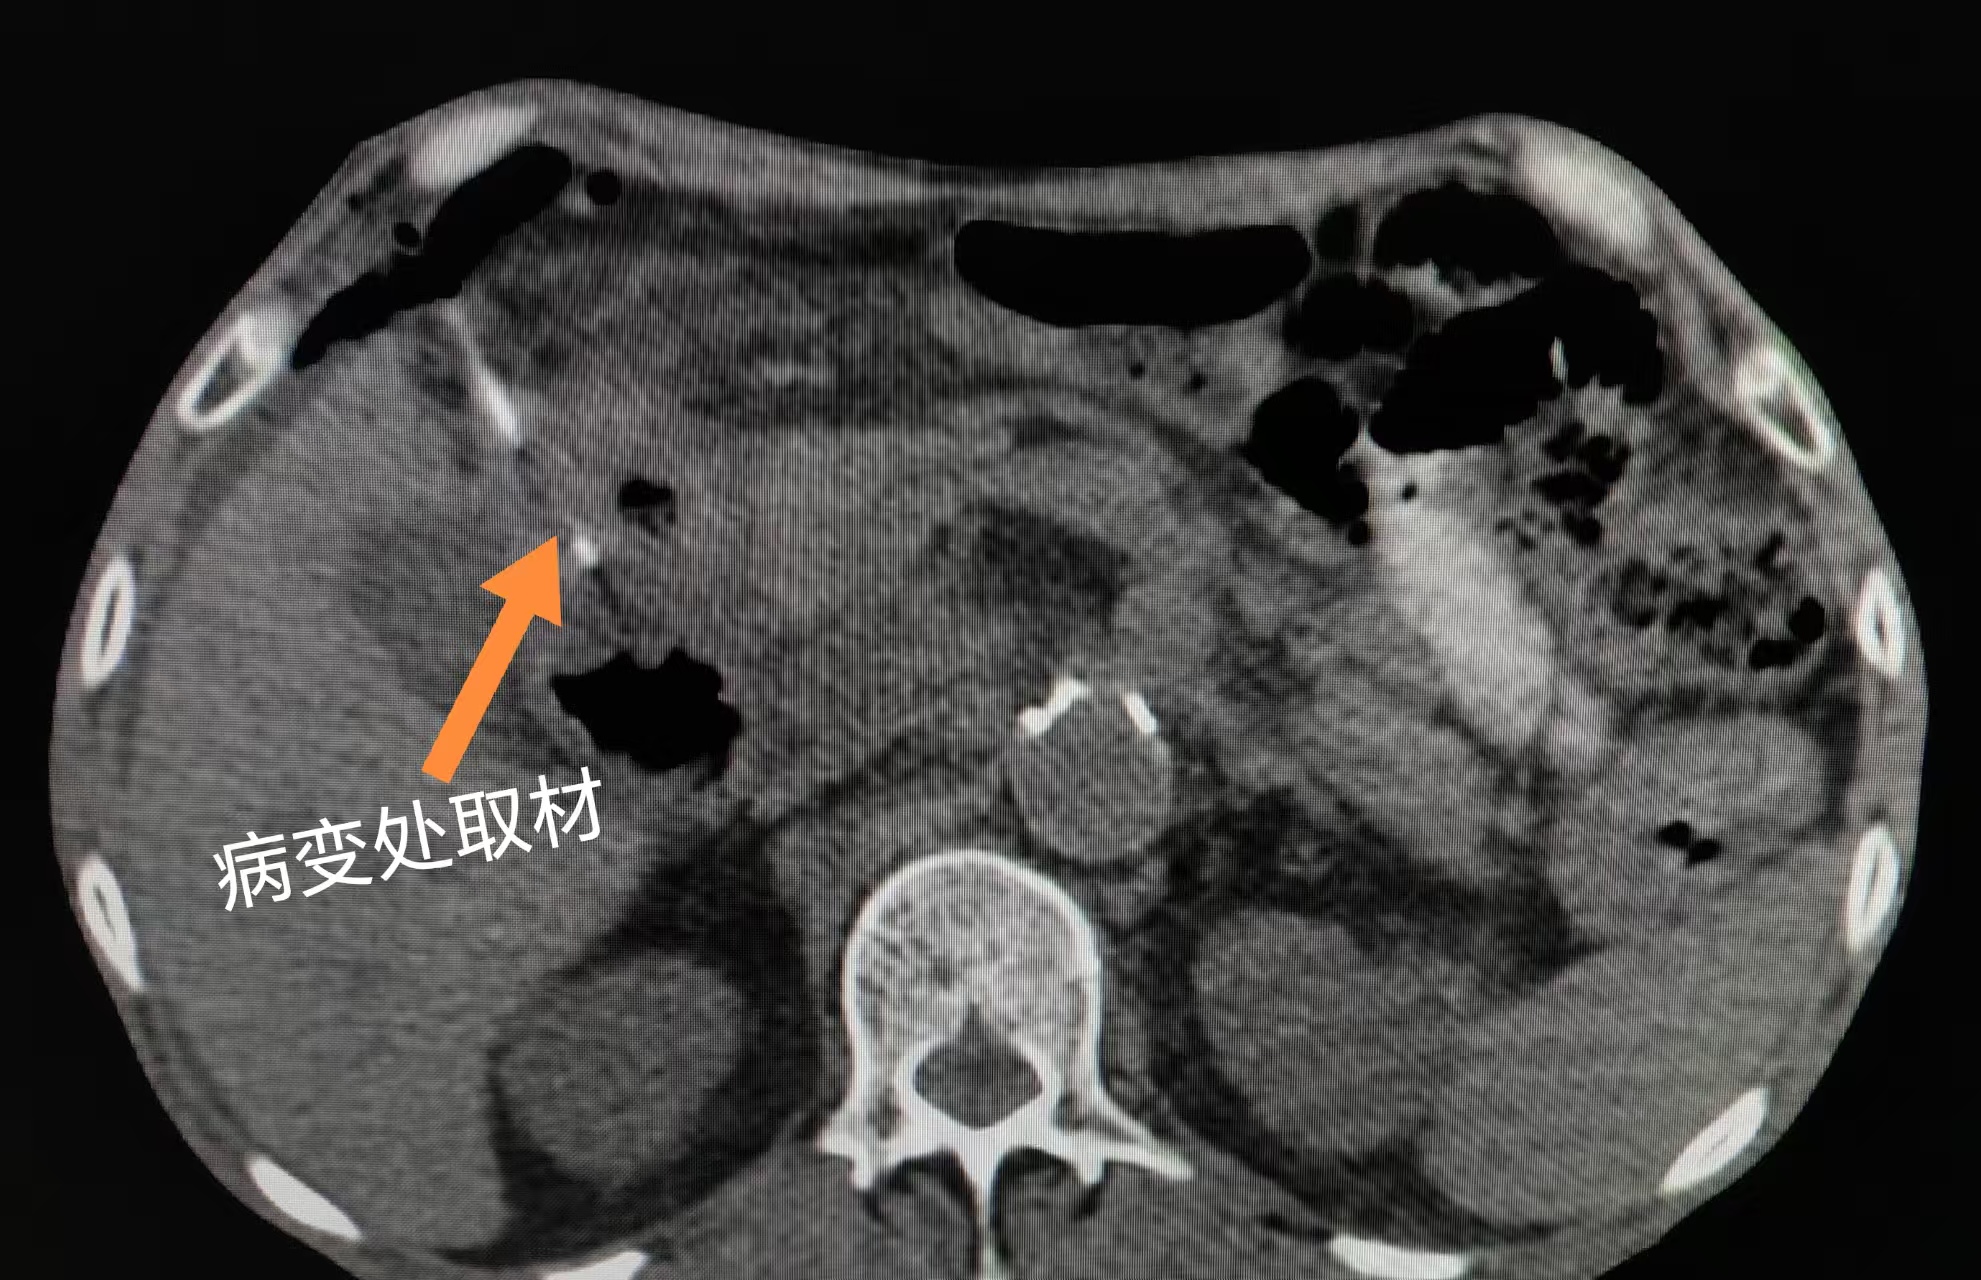

6月初,患者家属求助石景山医院肿瘤科张利锋主任。张主任综合研判患者影像学资料(CT、PET-CT),高度怀疑肠道恶性肿瘤,但亟需病理确诊。考虑到多次肠镜取检未果,张主任决定采用CT引导下结肠占位穿刺活检术。

6月10日,手术在CT实时引导下精准进行。张利锋主任操作细致,成功获取病变组织。术后患者无任何不适,病理结果明确为结肠腺癌。患者随即依据该诊断,开始规范化抗肿瘤治疗。